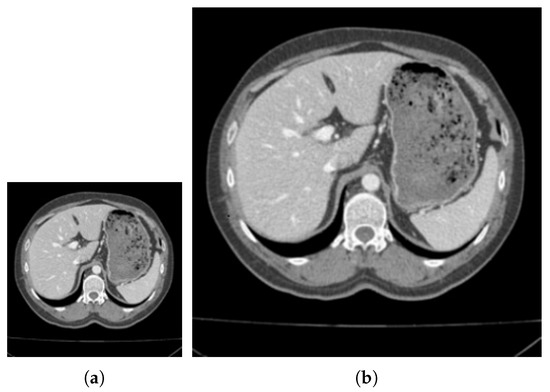

Fast Segmentation of Vertebrae CT Image Based on the SNIC Algorithm

by Bing Li, Shaoyong Wu, Siqin Zhang, Xia Liu and Guangqing Li

Tomography 2022, 8(1), 59-76; https://doi.org/10.3390/tomography8010006 - 3 Jan 2022

Automatic image segmentation plays an important role in the fields of medical image processing so that these fields constantly put forward higher requirements for the accuracy and speed of segmentation. In order to improve the speed and performance of the segmentation algorithm of [...] Read more.

Automatic image segmentation plays an important role in the fields of medical image processing so that these fields constantly put forward higher requirements for the accuracy and speed of segmentation. In order to improve the speed and performance of the segmentation algorithm of medical images, we propose a medical image segmentation algorithm based on simple non-iterative clustering (SNIC). Firstly, obtain the feature map of the image by extracting the texture information of it with feature extraction algorithm; Secondly, reduce the image to a quarter of the original image size by downscaling; Then, the SNIC super-pixel algorithm with texture information and adaptive parameters which used to segment the downscaling image to obtain the superpixel mark map; Finally, restore the superpixel labeled image to the original size through the idea of the nearest neighbor algorithm. Experimental results show that the algorithm uses an improved superpixel segmentation method on downscaling images, which can increase the segmentation speed when segmenting medical images, while ensuring excellent segmentation accuracy. Full article